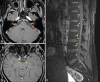

Neurolymphomatosis as a Presenting Feature of Primary Testicular Lymphoma